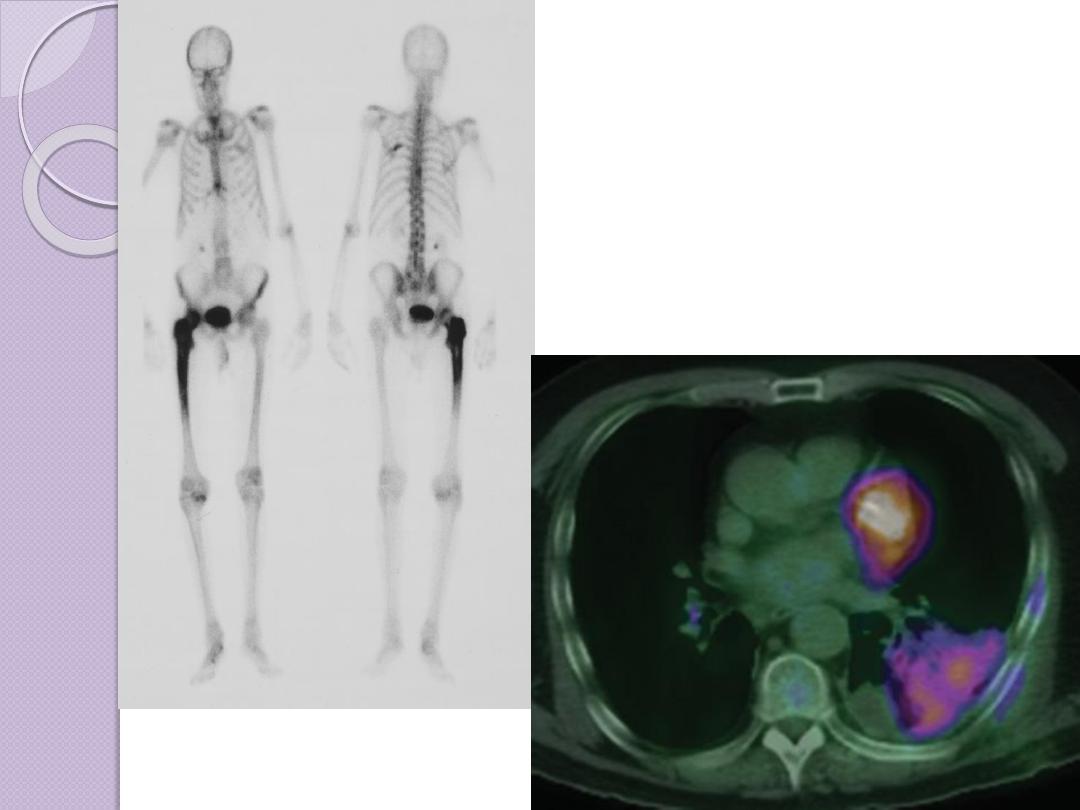

NUCLEAR MEDICINE

Nuclear medicine images are made by giving the patient

a short-lived radioactive material. The most

commonly used radionuclides decay rapidly and have

half-lives of only hours. Most materials administered

are not detectable within a day or so after

administration.

Nuclear medicine images are made by a gamma camera

or positron emission scanner that records radiation

emanating from the patient and makes an image of

the distribution of the radioactive material . The

major advantage of nuclear medicine is its ability to

obtain an image of physiologic function. For example,

virtually no other imaging technique can assess

regional pulmonary ventilation or hepatobiliary

function.